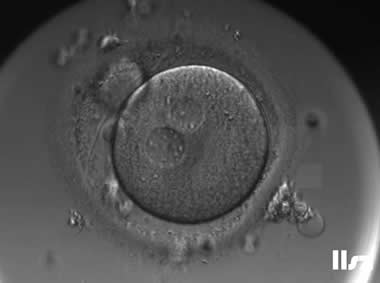

1. GV卵母细胞

细胞核未破裂,核膜完整,可见较大的生发泡;处于第一次减数分裂前期,染色体未排列到赤道板;线粒体分布不均,胞质内脂滴较多,皮质颗粒未完全迁移至质膜下。

无法自发完成减数分裂,不能直接受精;若体外培养至成熟(IVM),成功率低,胚胎染色体异常风险高;通常需体外成熟培养,但发育潜能较低。

| |

| GV卵母细胞:该枚卵子从GV卵发育为MI卵,然后从MI卵发育为MII卵。 | |